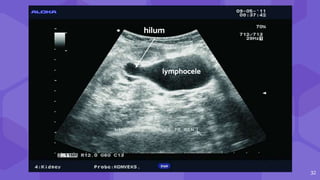

hilum

lymphocele

33